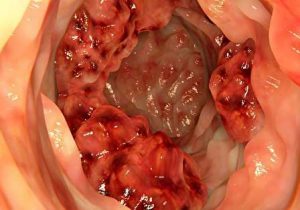

سرطان روده بزرگ و هرآنچه باید درباره آن بدانید

راههای تشخیص و درمان سرطان روده بزرگ

علت و علائم سرطان روده بزرگ چیست؟